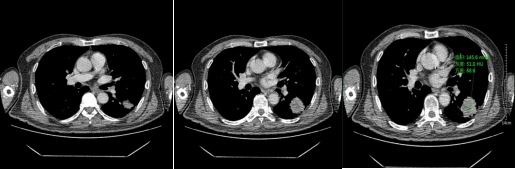

動脈期

靜脈期

以上肺結節(jié)影像表現(xiàn),只要出現(xiàn)其中一項或兩項,我們就要高度懷疑結節(jié)惡性,需要進一步CT增強檢查,排除結節(jié)的良惡性,更全面了解結節(jié)的性質。

對于實性結節(jié)、亞實性磨玻璃結節(jié)具有以上惡性征象,就需要進一步CT增強掃描。增強CT的意義在于觀察結節(jié)與周圍血管的關系,結節(jié)本身有沒有血供及血供的程度。因此,需要專業(yè)醫(yī)師根據(jù)結節(jié)強化的方式、程度,結節(jié)本身的形態(tài)特征,與周圍組織的關系,全面評估結節(jié)的性質,判斷結節(jié)良惡性,為患者的治療制定下一步措施。